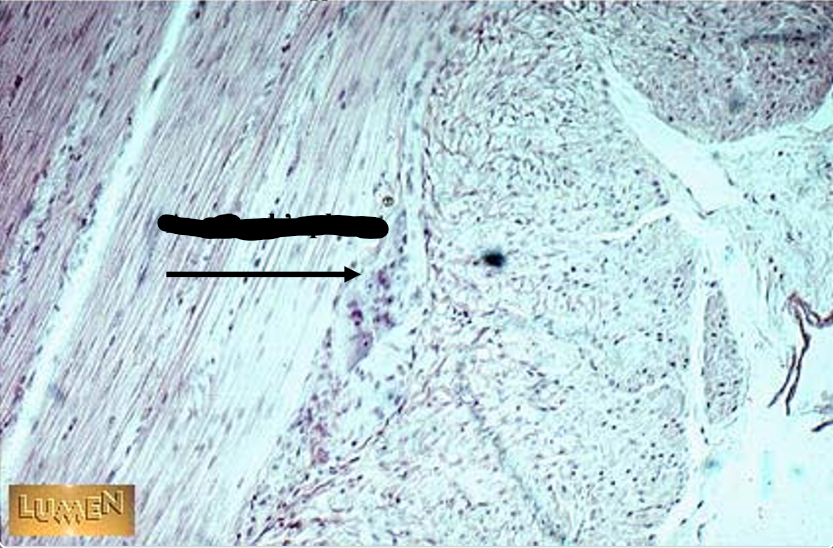

the arrow points to

Auerbach’s plexus